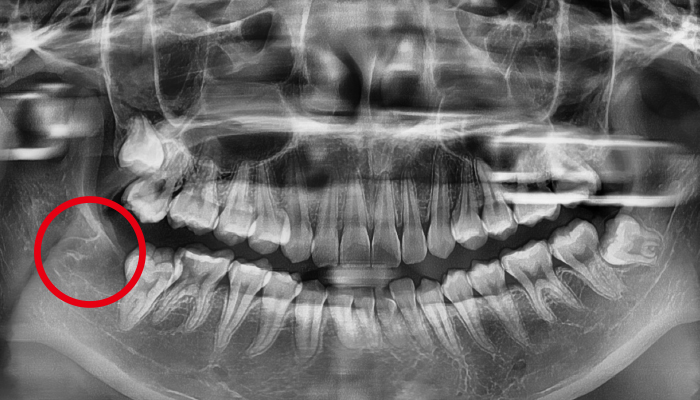

사랑니 발치 전후 사례

• 치료전

치료후